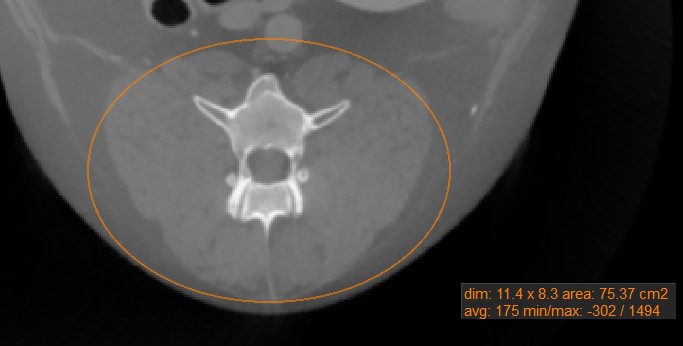

Oval

../_images/image4.jpg

Mark oval areas of the active image slice by using the Oval measurement tool.

Select the Oval tool and assign it to one of the available mouse buttons. Start the measurement by pressing on the active image slice and drag the mouse to obtain an oval shape. Release the mouse when satisfied with the size of the marked area.

All available measurement values are displayed alongside the measurement.

Modify the marked area by moving one of the four points describing the rectangle around the oval shape using the Default tool.